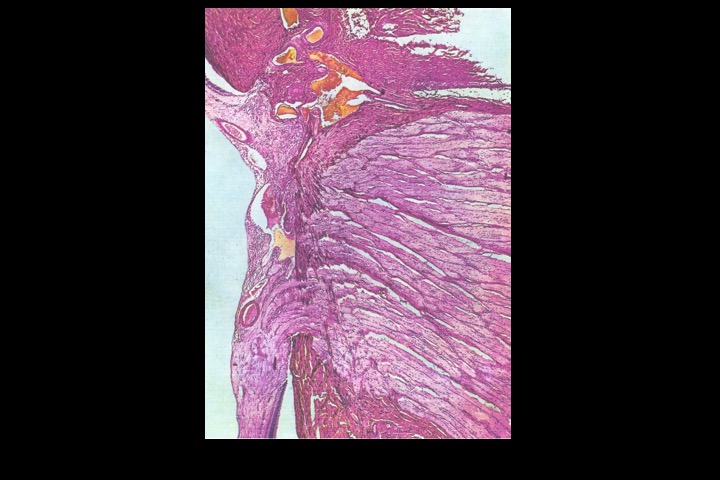

Disco do nervo óptico_2